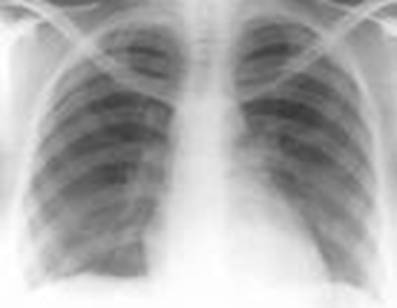

Пациент 54 года

Отёк легких